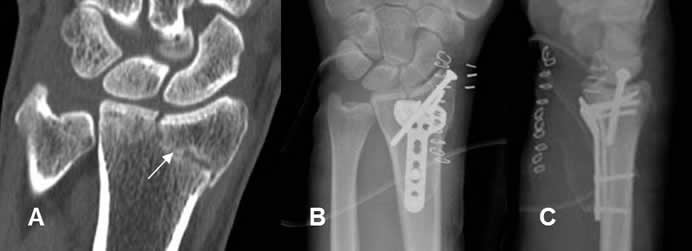

Fig 105. Fijación interna.

A: TAC reconstrucción coronal. Fractura de la estiloides radial no desplazada y con compromiso intra-articular.

B: Rx AP y C: Rx lateral. Fijación de la fractura con placa de compresión y tornillos.